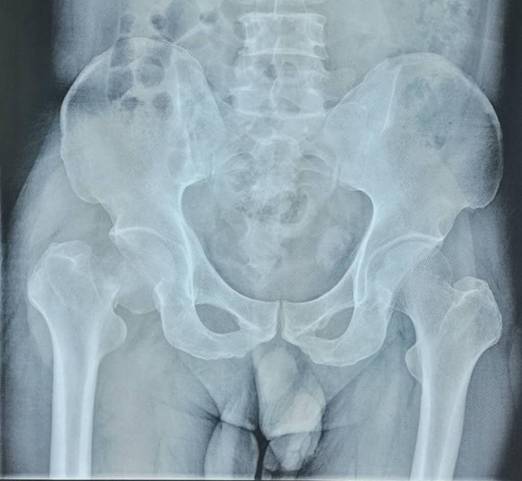

全髋关节置换术治疗股骨头坏死

优点:手术成熟,疗效确切。

髋关节外科脱位技术治疗股骨头无菌性坏死

优点:直接去除坏死骨质,植入新鲜骨,治愈率高。

术前术后对比

全髋关节翻修术